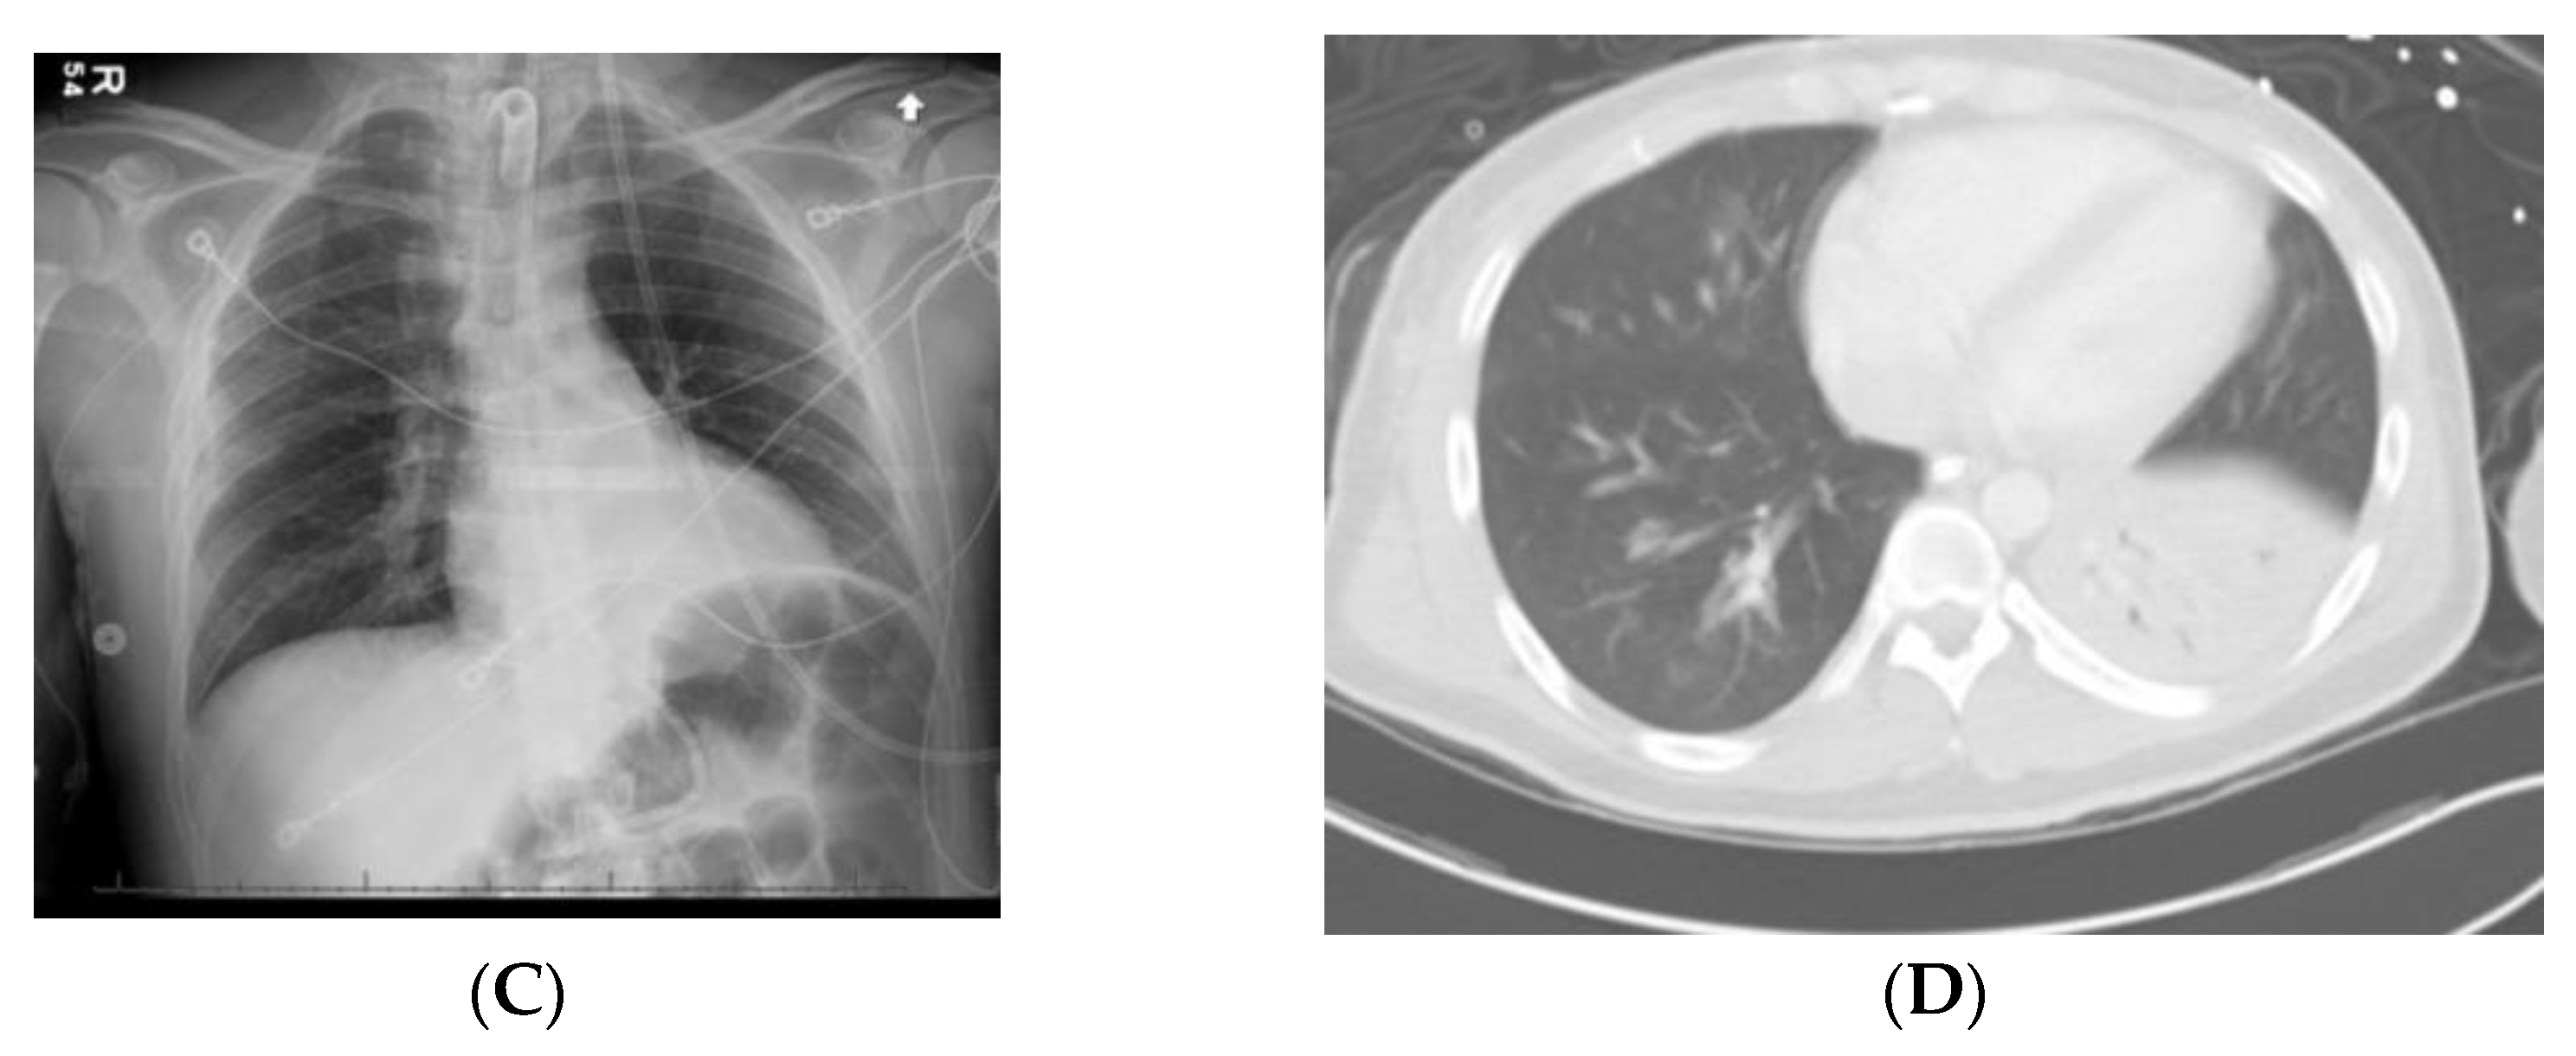

6.1. Case 1

6.2. Case 2